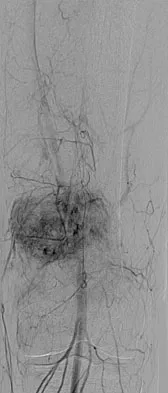

Figures 20a and 20b show the AP and lateral radiographs of a 62-year-old man who has had hip pain for the past 3 weeks. Figure 20c shows a CT scan of the abdomen and pelvis. A needle biopsy specimen is shown in Figure 20d. Preoperative management should include which of the following?

Explanation

The histology shows findings consistent with metastatic renal cell carcinoma. Renal cell carcinoma metastases are extremely vascular. Preoperative embolization helps minimize the amount of blood loss during curettage of these lesions. Chatziioannou AN, Johnson ME, Pneumaticos SG, et al: Preoperative embolization of bone metastases from renal cell carcinoma. Eur Radiol 2000;10:593-596.